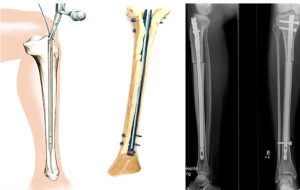

При осмотре отмечаются отек правого коленного сустава и верхней трети голени, болезненность при пальпации и положительный симптом баллотации правого надколенника. После клинико-рентгенологического обследования установлен диагноз: закрытый внутрисуставной чрезмежмыщелковый перелом правой большеберцовой кости со смещением отломков, тип 41С1 (рис. 1, I).

Сосудистых и неврологических расстройств в дистальных отделах правой нижней конечности не выявлено. При поступлении произведена анестезия места перелома, при пункции правого коленного сустава получено 60 мл крови с примесью жира, выполнена внешняя иммобилизация конечности гипсовой лонгетной повязкой. На следующий день под наркозом произведена операция: закрытая репозиция и чрескостный остеосинтез правой большеберцовой кости стержневым аппаратом конструкции А.И. Городниченко. Через разрезы кожи и мягких тканей по передневнутренней поверхности правой голени длиной до 8 мм введено три спонгиозных стержня в мыщелки большеберцовой кости и три кортикальных стержня в диафизарную часть. После фиксации проксимальных стержней в аппарате под контролем электроннооптического преобразователя произведена закрытая репозиция с помощью съемных рукояток с последующей стабилизацией дистальных стержней (рис. 1, II). Кожа вокруг стержней ушита одиночными швами.